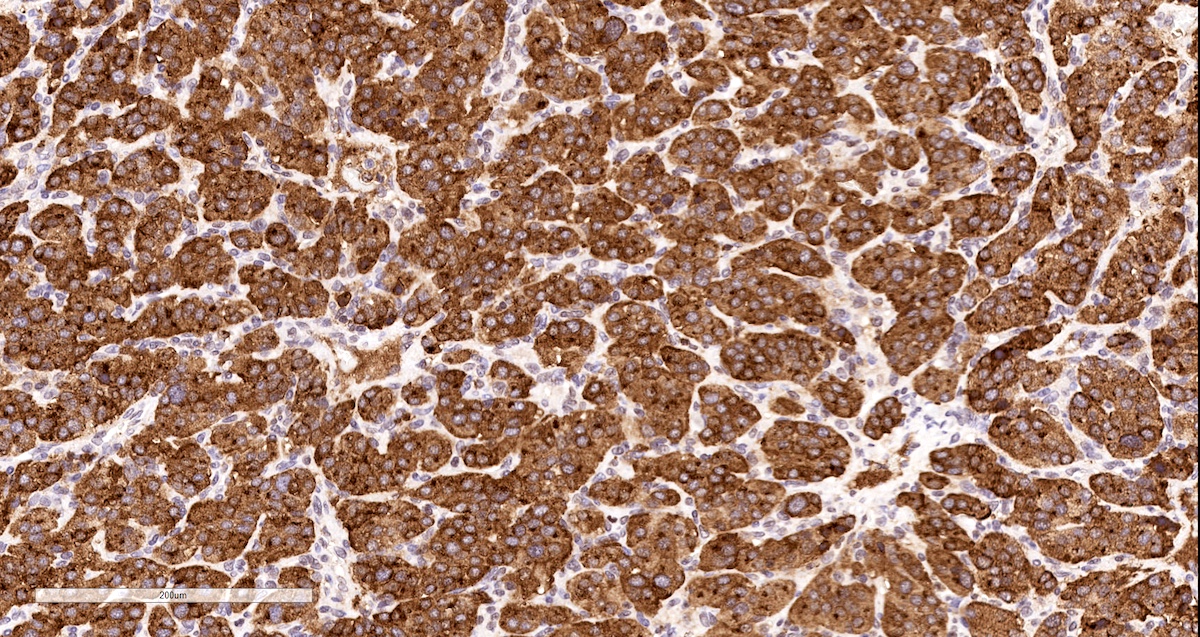

Positive stains

- INSM1 (diffuse nuclear) (Am J Surg Pathol 2018;42:665)

- Chromogranin A (can be only focal or perinuclear dot-like golgi pattern)

- Synaptophysin (Histol Histopathol 1993;8:429)

- CD56 (Endocr Pathol 2002;13:149)

- S100 may be diffusely positive (J BUON 2018;23:1540)

- GATA3 (diffuse nuclear) (Hum Pathol 2020;103:72, Am J Surg Pathol 2014;38:13, J Clin Med 2018;7:280)

- Tyrosine hydroxylase (critical enzyme required for catecholamine synthesis; usually diffuse and strong in sympathetic paragangliomas, may be weak or focal in parasympathetic tumors) (Hum Pathol 2020;103:72)

- Dopamine beta hydroxylase and phenylethanolamine N methyltransferase (PNMT) (epinephrine producing tumors) (see Diagram below) (Neuroendocrinology 2015;101:289, J Clin Med 2018;7:280)

- Sustentacular cells: S100, GFAP and SOX10 (Hum Pathol 2020;103:72)

- IHC surrogate markers for germline mutations:

- SDHB or SDHA expression loss: germline SDHx mutations (Lancet Oncol 2009;10:764)

- FH expression loss: germline FH mutation (HLRCC) (Hum Pathol 2018;71:47)

- Carbonic anhydrase IX (CAIX) expression: 80% of VHL mutation (Mod Pathol 2020;33:57)

- Inhibin alpha: any hypoxic pathway disease (SDHx, VHL, etc.) (Am J Surg Pathol 2021;45:1264)

- Reticulin highlights the nesting pattern (Int J Gynecol Pathol 1991;10:203, Exp Toxicol Pathol 2013;65:631)

Contributed by Luvy Delfin, M.D. and Sylvia L. Asa, M.D., Ph.D.